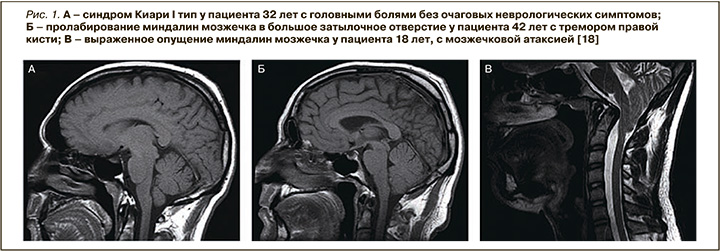

Мальформация Киари подразделяется на четыре типа. Некоторые авторы выделяют также пятый тип, так называемый тип 0 [12]. В рамках данного материала мы рассмотрим типы 0 и I (рис. 1) в связи с тем, что эти типы мальформации Киари редко диагностируются. Связано это с тем, что в 90% случаев они протекают малосимптомно или бессимптомно, в том числе в комбинации с сирингомиелией [10, 16]. В то же время II, III, IV типы в большинстве случаев имеют ярко выраженные, специфические врожденные клинические проявления:

- тип 0: структуры заднего мозга доходят до уровня большого затылочного отверстия/задняя затылочная ямка уменьшена в размерах;

- I тип: миндалины мозжечка опускаются в большое затылочное отверстие до 5 мм;

- II тип: ствол головного мозга, четвертый желудочек, а также миндалины мозжечка смещаются в большое затылочное отверстие более чем на 6 мм, с расщеплением позвоночника;

- III тип: грыжа мозжечка с вовлечением/без вовлечения структур продолговатого мозга;

- IV тип: мозжечковая гипоплазия или аплазия с сохранной задней черепной ямкой без грыжи структур заднего мозга [10].